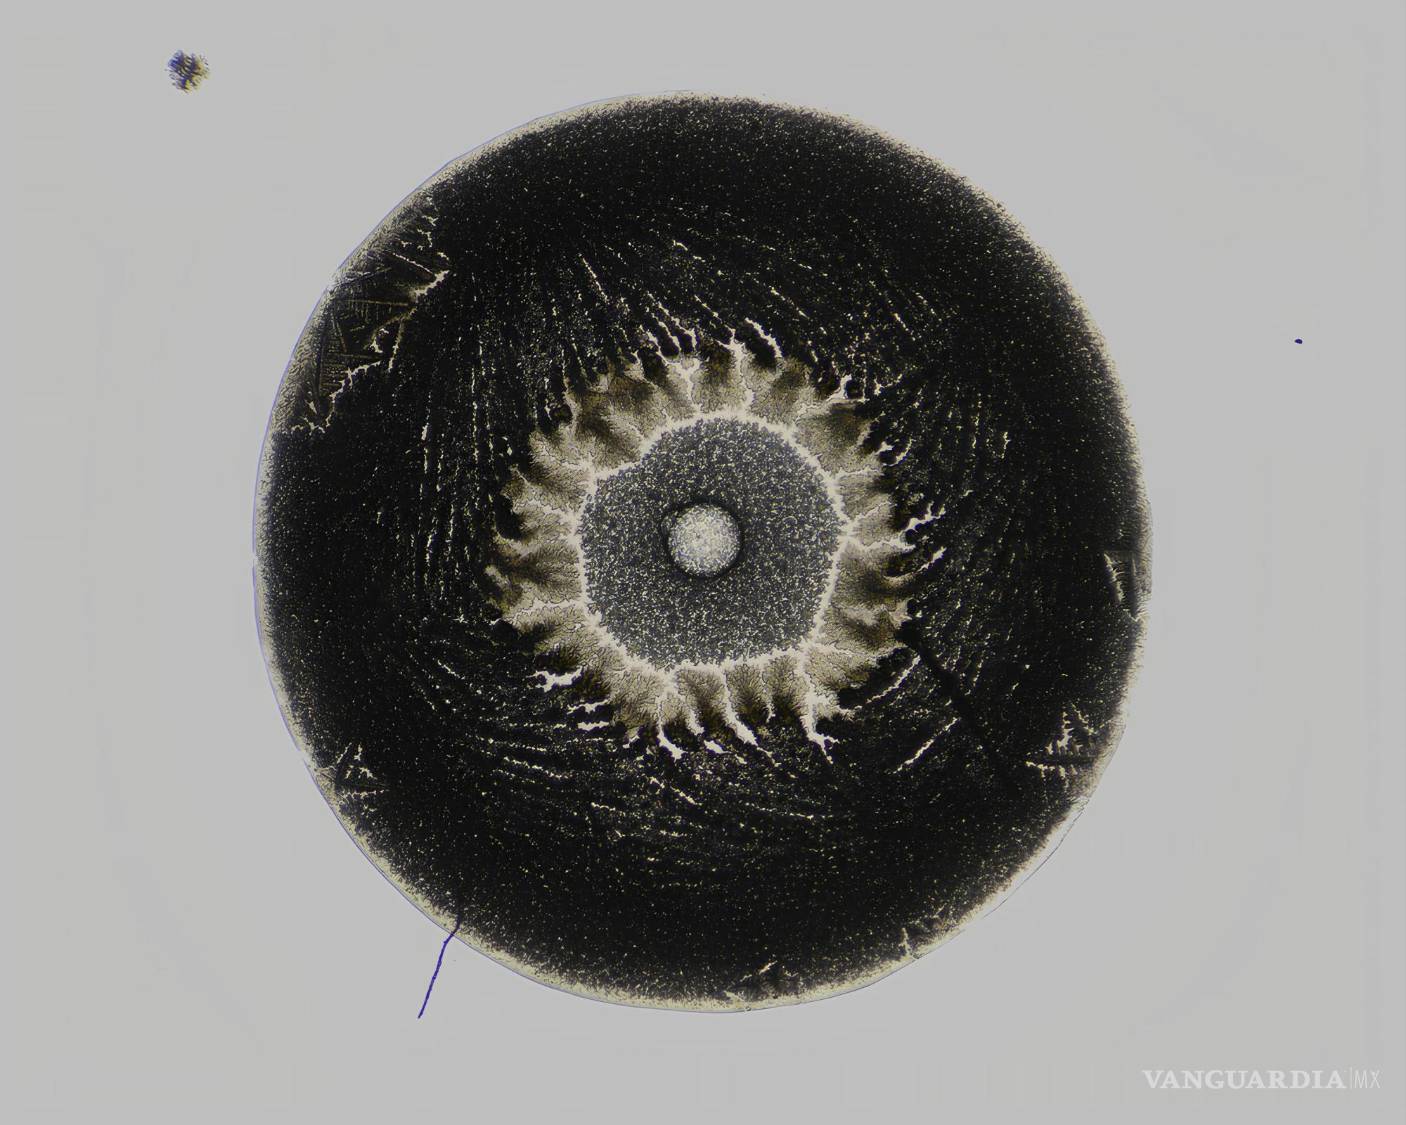

Las personas científicas ponían muestras acuosas, cosas que están mezcladas con agua, como sangre, una lágrima, medicamento, entonces se ponen en un portaobjetos con micropipetas y las gotitas que quedan las ponen a secar. Y el residuo lo toman en microscopio o en otros medios científicos digitales para poder ver qué se formó.

Sangre cruda, lágrimas, suero sanguíneo, plasma, antibióticos, ciprofloxacino, vacuna covid. Tenemos medicamentos y fluidos corporales.

Lo que busca este grupo de científicos es que se pueda diagnosticar enfermedades como pueden ser las cardiovasculares o cáncer a través de la sangre.

También buscan encontrar trastornos metabólicos con las lágrimas y otro de los objetivos es el control de calidad de muchos tipos de medicamentos que se encuentran en la farmacia u otros que son basados en medicina por plantas.

Imagen Obra1

$!Vacuna del COVID-19 + agua (2024)